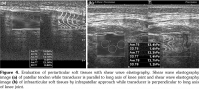

All patients and healthy volunteers were screened with Canon Aplio 500 Platinum US device (Canon Medical Systems, Tokyo, Japan) equipped with SMI, PD and SWE functions. All participants were examined in supine position and their knees were in extension (Figures 1, 2). Once the gray scale US examination confirmed the arthritis based on synovial thickening, joint effusion and periarticular echogenicity, then SMI and SWE were performed to the supraarticular and infraarticular soft tissues concerning the synovium and periarticular soft tissues. VI is a novel parameter determined for SMI and PD corresponding the ratio of colored pixels to the total pixels within the selected region of interest (ROI). VI was calculated automatically on colored SMI and PD images over the selected rectangular shaped ROI with edges measured 5x15 mm (Figure 3). Mean VI values were calculated by averaging results of three different acquisitions of PD and SMI. The ROI was placed perpendicular to the long axis of the knee joint at the supraarticular and infraarticular locations including the synovium and periarticular soft tissues. On SWE evaluation, the QT and PT were demonstrated along with their long axis. Three different ROIs for SWE were performed from the tendon halves closer to the knee joints. Each ROI was in circle shape and 3 mm in diameter. We depicted mean elasticity for PT, QT, supraarticular soft tissues (SAST) and infraarticular soft tissues (IAST) (Figures 4, 5).

No statistically significant difference was found between the mean ages of study and control subjects. Mean VI values in the study group obtained from SAST including synovium and suprapatellar fat pad were 8.2±3.4% for SMI and 9.1±3.1% for PD. Those were found as 2.9±1.4% for SMI and 3.4±1.4% for PD in the control group. When the study and control groups were compared, there was a statistically significant difference between VI values determined by SMI (p<0.001) and PD (p<0.002), respectively. In the study group, mean VI values obtained from IAST including synovium and infrapatellar fat pad were 7.9±3.1% for SMI and 8.1±2.8% for PD. Those were found as 2.6±1.5% for SMI and 3.1±1.5% for PD in the control group. There was a statistically significant difference for VI values of IAST via SMI (p<0.001) and PD (p<0.003) among the study and control groups, respectively. A comparison of overall VI values obtained from both study and control group participants did not show any statistically significant difference among mean values (p>0.05).